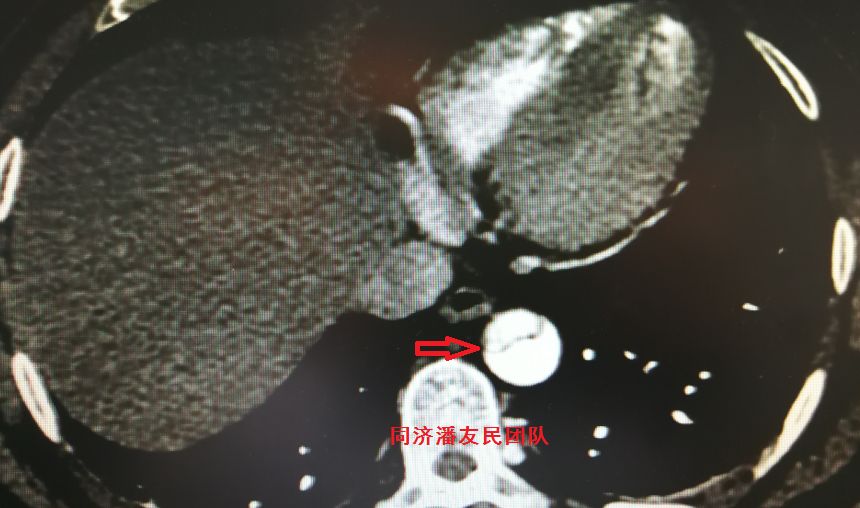

结果在上级医院复查胸腹主动脉CTA,在平扫CT提示主动脉夹层的对应层面,证实了主动脉夹层(图3~6)。同时发现升主动脉及主动脉弓均有夹层撕裂 (图7~8) 。 因此,正确诊断应该是 A型 (1型) 主动脉夹层。

图7 :CTA显示主动脉弓层面夹层撕裂内膜片(红箭头所示)